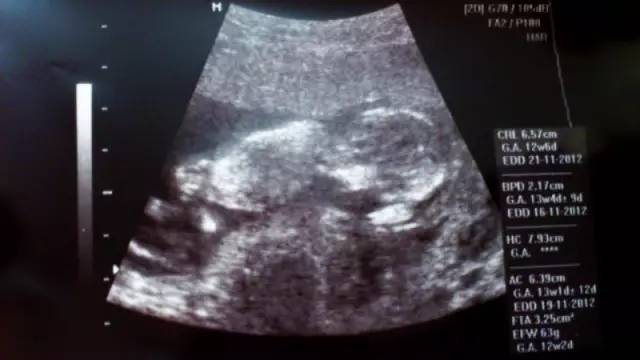

胎儿的畸形成千上万种,各种畸形都有。从大的范围来说,胎儿畸形包括染色体畸形和形态畸形这两个方面,从超声检查的原理来说,只有形态畸形是超声诊断的范围,但是某些染色体畸形伴随形态畸形的也在超声诊断范围内。实际上,在临床中,能检查出来的胎儿畸形很少。

我国卫生部制定了超声检查规范,重点强调了致死性胎儿畸形的检查。致死性的胎儿畸形包括无脑儿、明显的脑膨出、明显的脊柱裂、胸腹壁缺损、内脏膨出、致死性的软骨畸形等,只有这几种是医生应该能诊断出来的。其他的一些畸形可能会在一些医生、一些医院诊断出来,但不是所有的医院、所有的医生。这也是目前胎儿超声检查的一个问题,这种现实与广大孕妈妈的要求相距甚远,这是现存的差距。